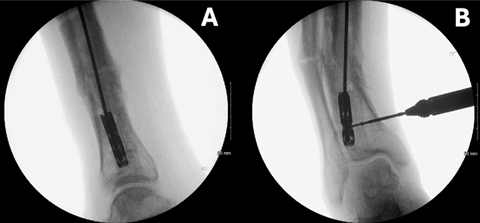

手术案例1:一例51岁男性胫骨骨不连患者断裂胫骨髓内钉的取出过程

A. 侧位像显示导丝通过选定螺钉孔向远端置入。

B、C. 逐步置入微型螺钉。

D. 取出远端断裂髓内钉。

E. 影像学确认成功取出。